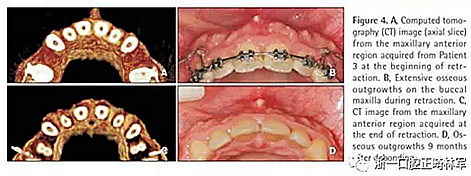

22歲,女性,主訴是牙齒不美觀?;颊叩那醒狼皟A,I類磨牙關(guān)系,深覆蓋,淺覆合。丙肝攜帶者,在接受疫苗接種。目標(biāo)是減小切牙前傾,獲得理想的覆合覆蓋,減少唇前突。治療計(jì)劃是拔除4顆前磨牙。

在這名患者觀察到最廣泛和嚴(yán)重的骨增生,且在第一個(gè)月最明顯。拆除托槽9個(gè)月后,這些增生明顯消退但仍舊很明顯(圖4)。內(nèi)收耗時(shí)11個(gè)月。